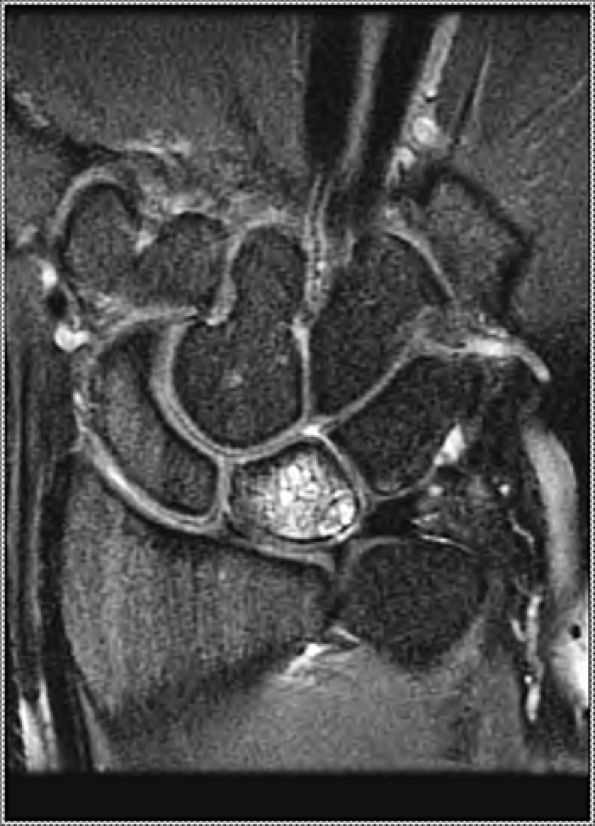

|